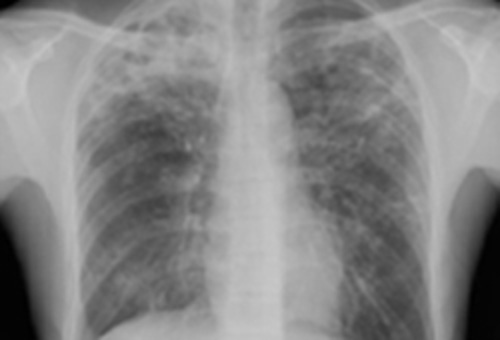

Туберкулез легких с кавернами

Рентгенография грудной клетки - Исследование первой линии при диагностике туберкулеза - Почти всегда отмечаются патологические изменения на рентгенограмме у иммуноскомпроментированных лиц. К типичным изменениям относятся фиброзно-очаговые затемнения в верхних долях с кавернами или без них - Нетипичный легочный рисунок может сопровождаться затемнением в средний или нижних долях, прикорневой или паратрахеальной лимфаденопатией или плевральным выпотом - Специалисты утверждают, что атипичные изменения на рентгенограмме являются скорее следствием иммуносупрессии, чем первичного туберкулеза - ВИЧ статус обуславливает лимфаденопатию, выпот, вовлечение нижних долей легких и милиарный рисунок; при этом каверны обнаруживаются реже. Отметим, что у больных с прогрессирующей ВИЧ инфекцией рентгенограмма может быть нормальной |

- Характерные отклонения при туберкулезе - Нехарактерные отклонения при туберкулезе - Норма |